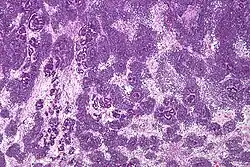

Patológicamente, un nefroblastoma consta de tres elementos:

- Blastema: una masa de células indiferenciadas capaces de crecimiento y regeneración en los órganos o partes del cuerpo, normalmente se encuentran en las primeras etapas de un organismo de desarrollo embrionario, y en la regeneración de tejidos, órganos y huesos.

- Mesénquima: un tipo de tejido conjuntivo reticular, que es de origen mesodérmico y situada en el mesodermo embrionario.

- Epitelio: el grupo de células que alinean las superficies del tumor.

El tumor de Wilms es un tumor maligno que contiene blastema metanéfrico, epitelio y estroma. Es característica su presencia en los glomérulos y túbulos renales rodeado por un estroma celular. El estroma puede incluir músculo estriado, cartílago, hueso, tejido graso y tejido fibroso. El tumor suele comprimir el parénquima renal normal.

El componente mesenquimal puede incluir células que muestran diferenciación rabdomioide, el cual puede por sí mismo mostrar elementos de malignidad: nefroblastoma rabdomiosarcomatoso.